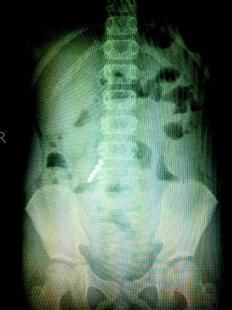

武昌区9岁男孩小彦(化名)半个月前,莫名出现腹痛的症状,起初家里人以为他是吃坏了肚子,可没想到孩子间断发烧了一个星期。家长带着孩子来武汉市儿童医院就诊,检查结果却让家长震惊了。CT结果显示,孩子右腹小肠肠管内竟然有5颗豌豆米大小的球状金属异物,一个紧挨着一个,肠液将其团团包裹在一起(如图)。这时小彦才说,原来他上学途中在路边摊上买过一包球状的吸铁石,样子像糖果,放在嘴里玩时不小心吞了进去,害怕爸爸妈妈说他,就没告诉大人。

为了防止病情恶化,医生立即对小彦进行腹腔镜手术,取出了这5颗磁铁,也将孩子小肠上穿孔坏死的地方进行了切除。昨日孩子的病情已经得到了控制,出院回家。

该院普外科卞红强主任医师介绍,在肠管蠕动过程中,吞进去的磁性玩具相互吸附,将肠膜黏在一起相互摩擦,导致肠穿孔及坏死,小彦发烧就是这样引起的。